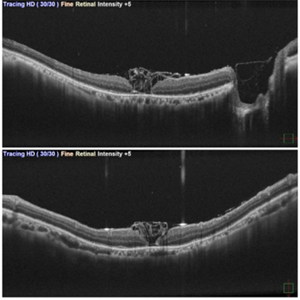

Inverted ILM Flap in RD with FTMH-First Post Op Day

Inverted ILM Flap in RD with FTMH-First Post Op Day

Oct 29 2024 by SHILPI H NARNAWARE, ICO ( Retina) , FAICO ( Vitreo-Retina)

OCT showing stuffed ILM under oil on first post op day in a case of RRD with FTMH.

Photographer: Shilpi Narnaware, Sarakshi Netralaya , Nagpur, Maharashtra , India

Imaging device: Mirante ( by Nidek)

Condition/keywords: FTMH, Inverted ILM technique, RD

Inverted ILM flap in RD with FTMH-First Post Op Day

Inverted ILM flap in RD with FTMH-First Post Op Day

Aug 23 2024 by SHILPI H NARNAWARE, ICO ( Retina) , FAICO ( Vitreo-Retina)

This is first post op day OCT of patient showing stuffed ILM in macular hole ,who underwent Vitrectomy with inverted ILM flap with silicon oil insertion in a case of RRD with FTMH.

Photographer: Shilpi Narnaware, Sarakshi Netralaya , Nagpur, Maharashtra , India

Imaging device: Mirante ( by Nidek)

Condition/keywords: FTMH, Inverted ILM technique, RD